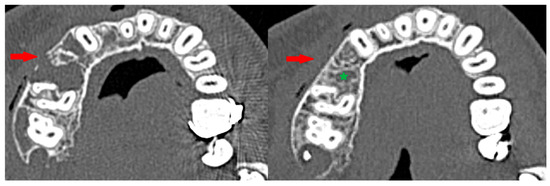

3.3. Osteosclerotic Rim (Peripheral Corticalization)